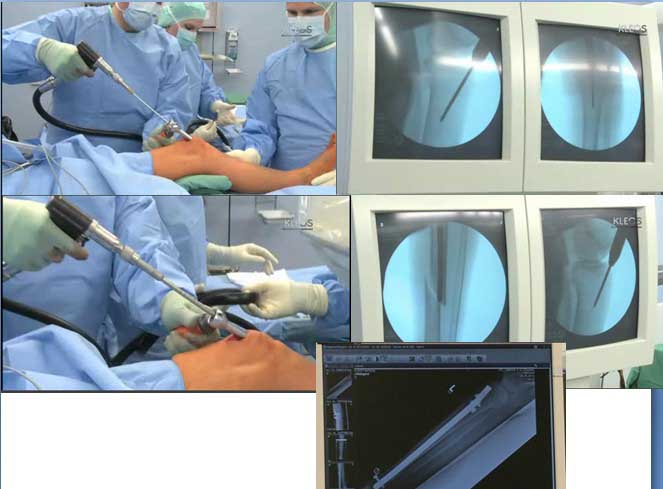

Заштифтовать большеберцовую кость при несгибающемся колене можно через расширенный доступ, то есть с артротомией. Это с подачи P.Tornetta считается оптимальным даже при нормальных движениях в колене, но при любых переломах в верхней трети.

кстати, о доступе: